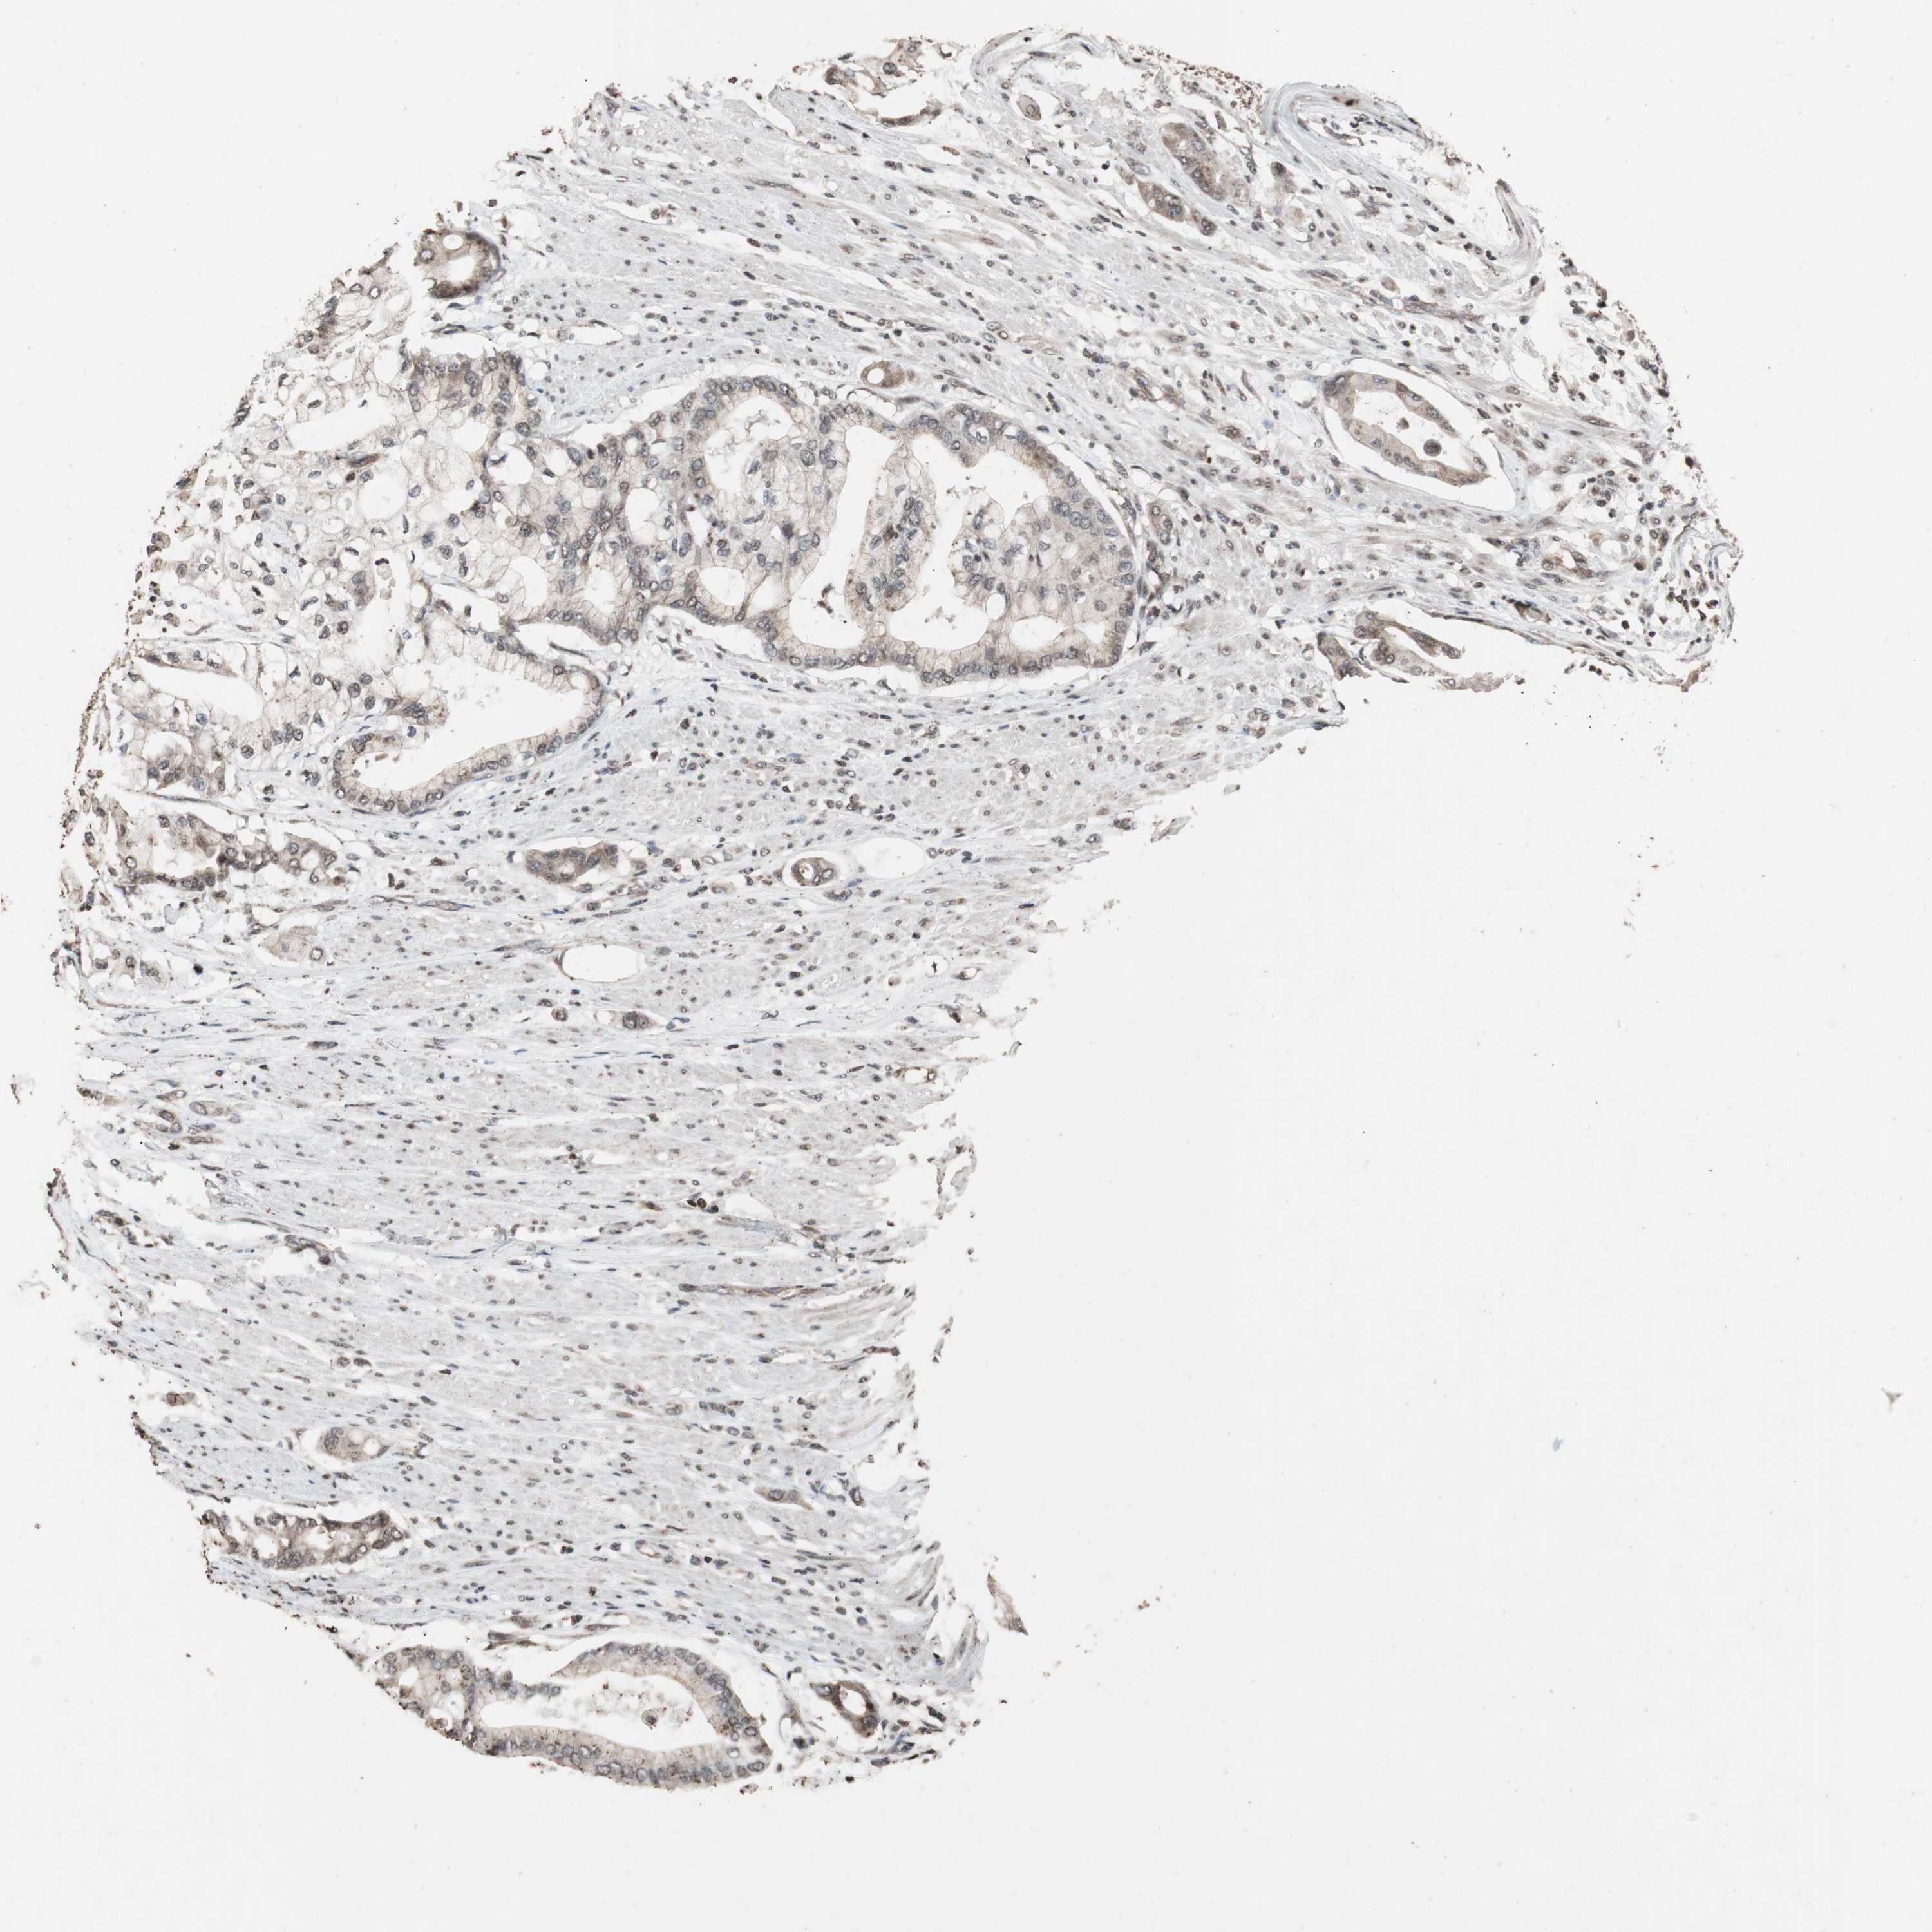

PANCREATIC CANCER - Protein expressioni

A mouse-over function shows sample information and annotation data. Click on an image to view it in a full screen mode. Samples can be filtered based on level of antibody staining by selecting one or several of the following categories: high, medium, low and not detected. The assay and annotation is described here.

Note that samples used for immunohistochemistry by the Human Protein Atlas do not correspond to samples in the TCGA dataset.

Antibody stainingi

Antibody staining in the annotated cell types in the current human tissue is reported as not detected, low, medium, or high, based on conventional immunohistochemistry profiling in selected tissues. This score is based on the combination of the staining intensity and fraction of stained cells.

Each image is clickable and will lead to virtual microscopy that enables deeper exploration of all samples and also displays staining intensity scores, fraction scores and subcellular localization as well as patient and tissue information for each sample.

Antibody HPA007072

Antibody HPA007151

Staining

High

Medium

Low

Not detected

Intensity

Strong

Moderate

Weak

Negative

Quantity

>75%

75%-25%

<25%

None

Location

Nuclear

Cytoplasmic/membranous

Cytoplasmic/membranous,nuclear

Adenocarcinoma, NOS

Adenocarcinoma, metastatic, NOS